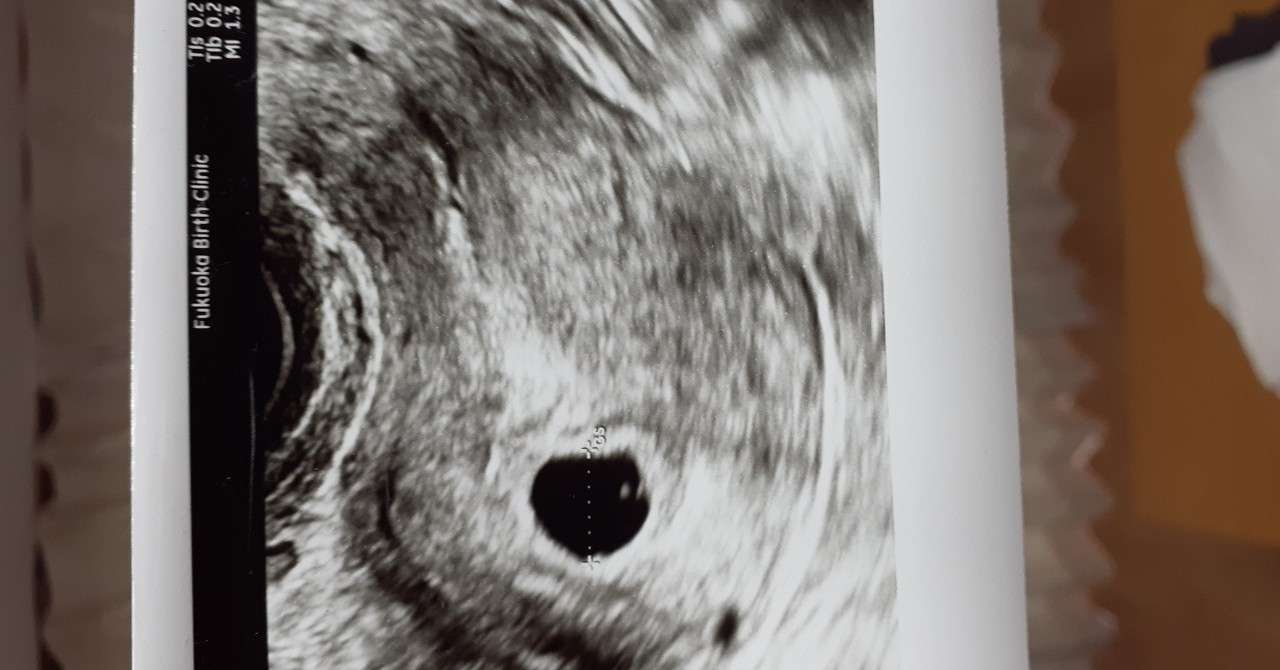

妊娠8週3日 8w3d の超音波 エコー 写真

妊娠5週3日 5w3d の超音波 エコー 写真

妊娠8週2日 8w2d の超音波 エコー 写真